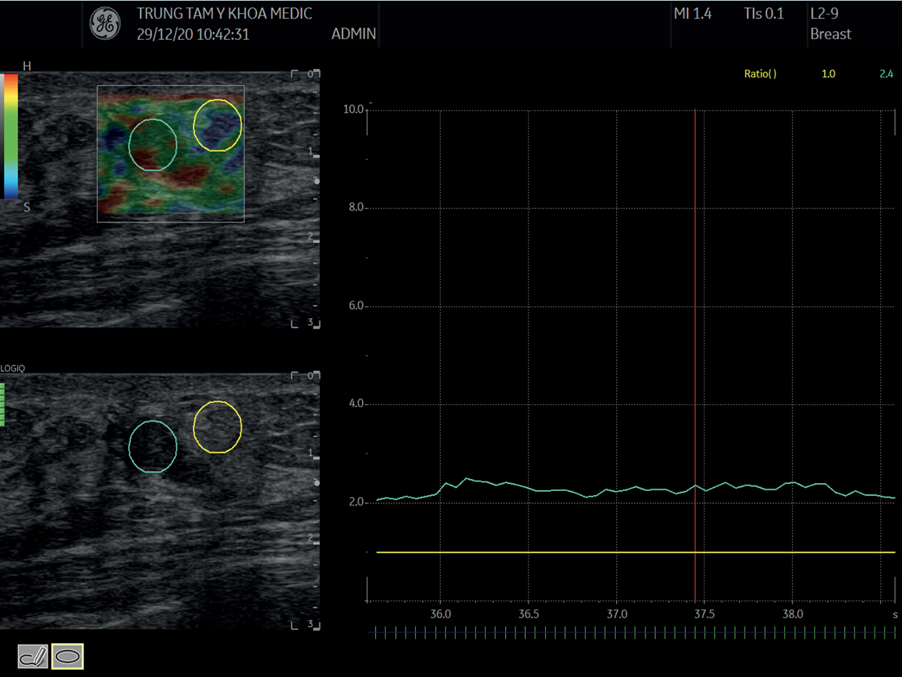

Kết quả Shear Wave Elastography 2D

Siêu âm đàn hồi định lượng cho thấy:

- Độ cứng khối u: 16,5 kPa.

- Độ cứng mô mỡ xung quanh: 6,82 kPa.

- Phần lớn giá trị kPa nằm trong ngưỡng an toàn (< 25–30 kPa).

Siêu âm đàn hồi mô định lượng 2D Shear Wave Elastography

Kết quả SWE không ghi nhận đặc điểm gợi ý ác tính giúp tăng độ tin cậy cho chẩn đoán tổn thương lành